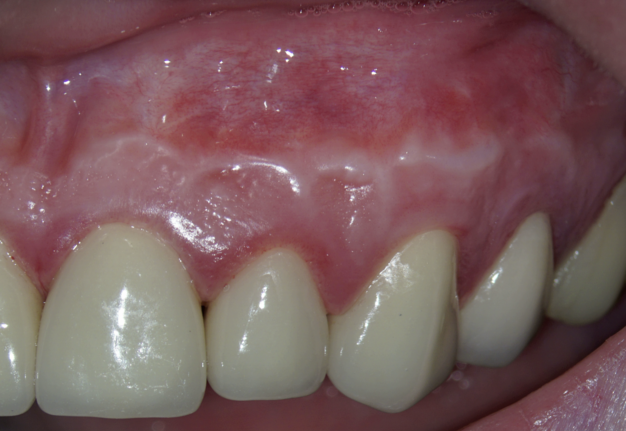

4. An unesthetic scar may form.

As a consequence of dehydration of the tissue, the Ochsenbein-Luebke flap sometimes tends to shrink during surgery resulting in tension and difficulty in replacing and securing it by suturing. Another disadvantage of the flap described in the literature is the risk of scarring (Fig 14) [7, 30].

According to Lavagnoli and Carnevale (1984), the cause of the scar visible on the attached gingiva is the inclination of the blade to the underlying bone [30]. If the blade is used at 90° to the bone, the incision will involve the epithelium and the periosteum, and the two scars will be superimposed one on top of the other so that they become visible. On the other hand, according to the two authors, if the incision is beveled, the periosteal scar will be covered by healthy epithelium, which will hide the underlying scar. We know today that this is an old theory based on the fact that the periodontists use beveled incisions and they don’t have scars. However, we know today that scarring doesn’t depend on the inclination of the blade, but rather on the correct repositioning of the flap, the precise suturing done under the operating microscope and the early removal of the sutures, as will be described later. In conclusion, the blade can be used at 90° to the bone and by following the above suggestions, there is no risk of scarring [5].

One of the less well-described, rare and late complications of the Ochsenbein-Luebke incision is the occurrence of fenestrations in the soft tissues with baring bone. These fenestrations can be located both in the area of ​​the attached gingiva, which corresponds to the horizontal component of the incision (Fig 15), and on the transition of attached gingiva into the alveolar mucosa, which corresponds to the vertical component of the incision (Fig 16).

The development of soft tissue fenestrations with associated bone exposure is predominantly linked to a thin gingival biotype, suboptimal flap design, and inadequate wound closure.